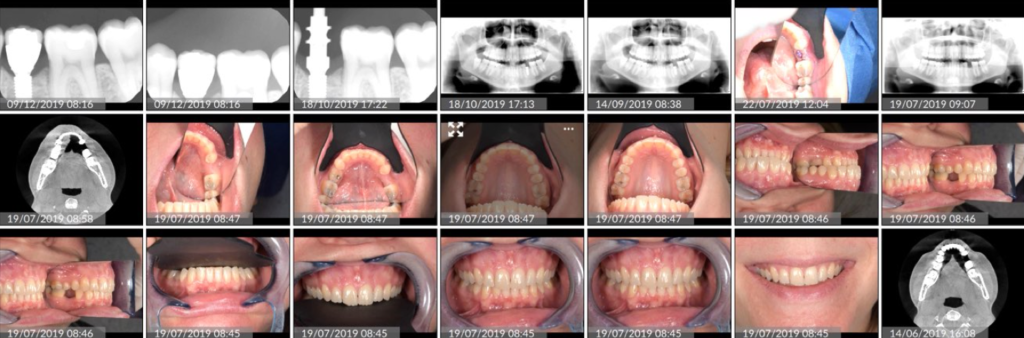

L’un des apports majeurs de la dentisterie digitale réside dans la qualité des données patient collectées au cabinet. Scanners intra-oraux, photographies cliniques, vidéos, radiographies 3D, face Scan ou encore enregistrements fonctionnels permettent aujourd’hui d’obtenir une vision extrêmement précise du cas clinique.

Ces données constituent ce que le Dr Noharet appelle le Clone Digital : une représentation numérique du patient, qui devient la base de tout travail clinique et prothétique. Contrairement aux méthodes analogiques, ce socle numérique limite les imprécisions, les pertes d’information et les interprétations subjectives.

Pour le prothésiste, cela signifie un accès à des informations complètes, cohérentes et exploitables dès le début du traitement.